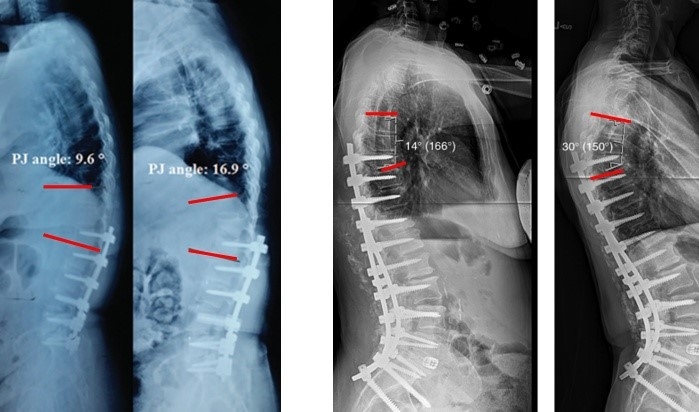

图18 固定近端交界性后凸角>5°

A:术前固定近端交界性后凸角>5°;B:上固定椎未跨过此区域;C:术后随访出现PJK